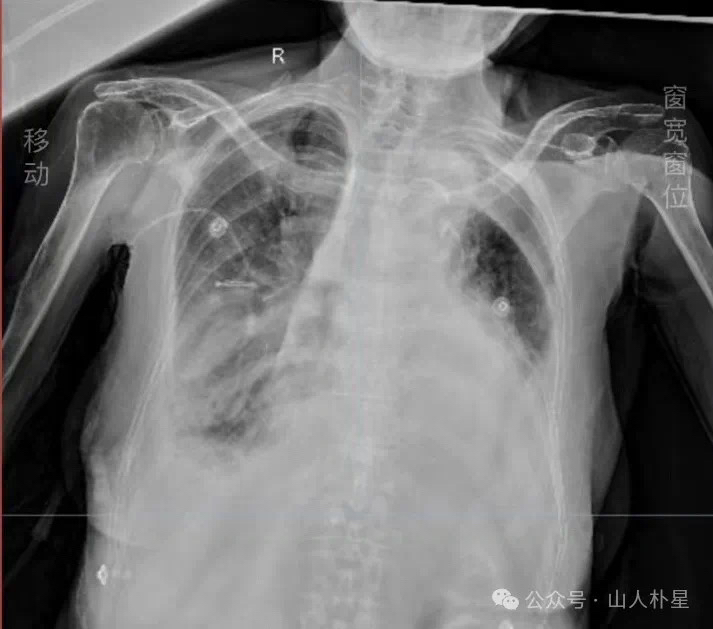

一周后虽仍是端坐呼吸,余症状均较前缓解,精神头不错,甚至跟家人聊了一下午天都不觉得累,说自己状态好!09-18复查胸片竟然还看到肺实质的改善。惊喜的跟大家分享这份喜悦,却没认识到法不可言,病情再次变化。